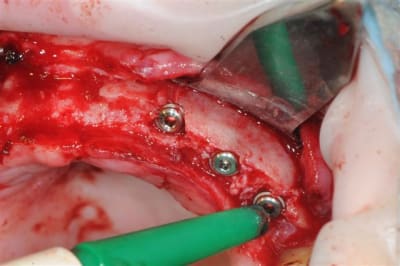

os magnifiquement vascularisé! excellente adhérence du greffon.

pas 40000, mais 2000 t/mn, ce qui n'est pas un bon plan pour les expanseurs meissinger, et à je crois bien provoqué un "m...e!" violent et la peur d'avoir tout explosé.

Mais non, mis à part une pénétration profonde (le spreader fait 15 mm pour une prévision d'implant de 10 mm)pas d'autres conséquence que des micros fractures crestale.

l'expansion en 22 à la jonction greffon os propre, faite à l'ostéotome manuel, malgré la non approbation de Thomas, c'est parfaitement passée, et nous avons constatés la parfaite liaison du bloc.